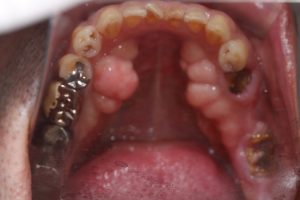

●骨隆起

●臼歯の歯冠、歯根の破折、隣接面カリエス

●咬合面 切端の咬耗

写真は、いずれもTCH(tooth contacting habit、上下歯列接触癖)の方の特徴ですが、40歳代くらいになると奥歯からトラブルが出てきて、喪失していきます。